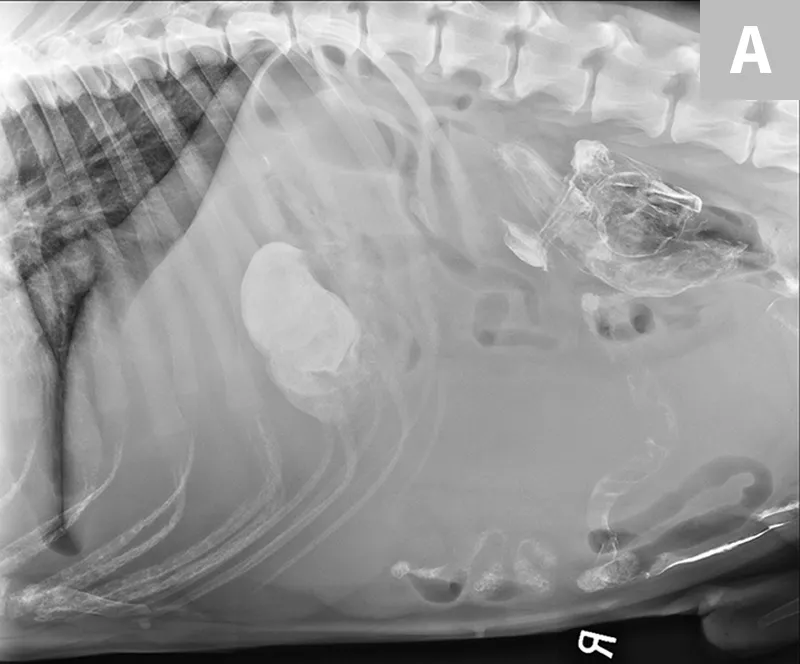

FIGURE 6

The spleen is markedly enlarged, hypoechoic, and lacy, with hyperechoic patches surrounding the hilus. A perivenous hyperechoic triangle at the splenic hilus is continuous with the mesentery, and no flow is present on Doppler. These findings are often associated with splenic torsion.20